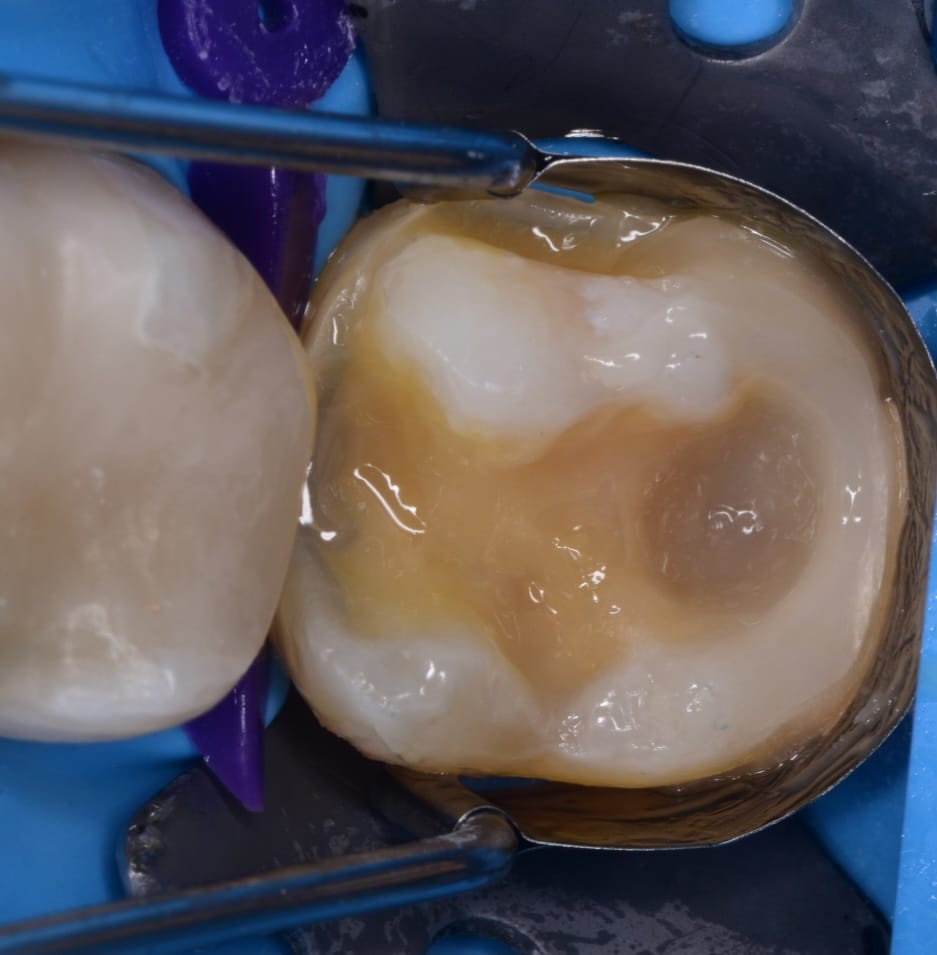

Immediate result

Direct view

Final result

Look to the fitness of the restoration on the tooth surface